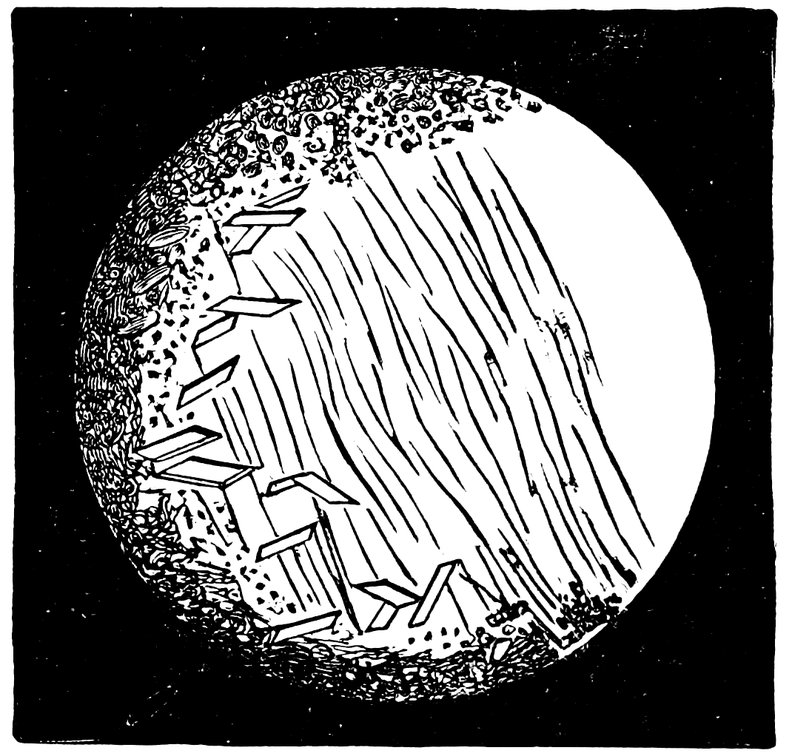

| 52. | Sagittal Section through the Cervix Uteri of a Woman twenty-six years of age. Dendriform branched glands | 217 |

| 53. | Cervix of a Woman seventy-two years of age, with glands that have undergone cystic degeneration | 217 |

| 54. | Sagittal Section through the Cervix Uteri of a Woman sixty-five years of age. The glands have undergone cystic degeneration | 217 |

| 92. | Sagittal Section through the Cervix of a Woman twenty-six years of age. Dendriform branched glands | 588 |

| 93. | Sagittal Section through the Cervix of a Woman sixty-five years of age. Glands which have undergone Cystic Degeneration | 589 |

| 94. | Cervix of a Woman seventy years of age. The Cervical Glands have undergone Cystic Degeneration | 589 |